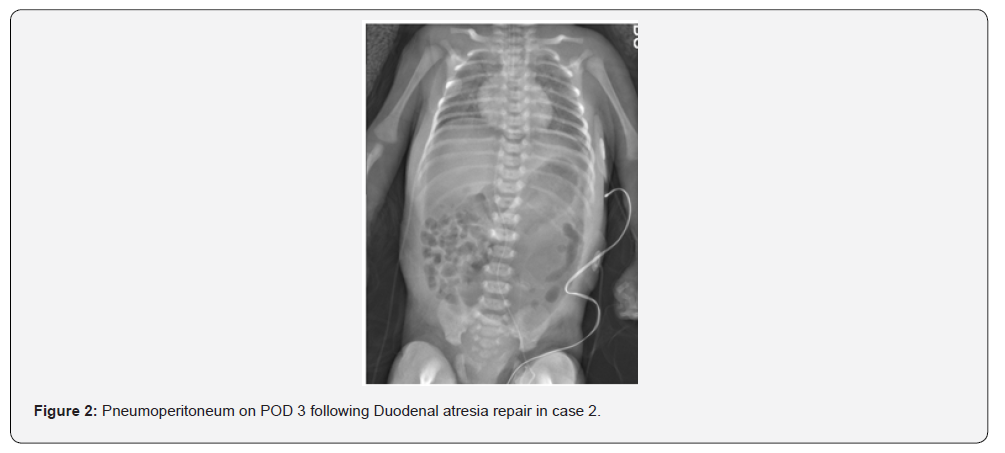

The first neonate, born at 31 weeks gestation with Trisomy 21, complete AVSD, pleural effusion, and duodenal atresia, was preoperatively on NI-NAVA. He was intubated for duodenal atresia repair and extubated to NI-NAVA on postoperative day two. On post-operative day four, he developed abdominal distention and hypoxemia; imaging revealed pneumoperitoneum (Figure 1). During laparotomy, worsening distention and hypoventilation prompted emergency abdominal drainage of gas and serous fluid. He required two doses of epinephrine and chest compressions briefly for bradycardia. A small anterior wall leak was repaired. Two months later, he underwent cardiac surgery and was eventually discharged home at six months of age. The second neonate, born at 37 weeks gestation and small for her gestational age, with duodenal atresia, myelomeningocele, and musculoskeletal deformities, underwent duodenal atresia repair where an annular pancreas was found. She was initially extubated to high flow nasal cannula, but within hours she required escalation of support to CPAP and then NIPPV. Seven hours post-extubation, she developed abdominal distension; imaging showed pneumoperitoneum (Figure 2). Re-exploration revealed a leaking anastomosis due to suture dehiscence, which was then repaired. She was successfully extubated to room air on postoperative day five and tolerated feeds.